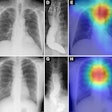

DL algorithm estimates lung nodule cancer risk, reduces false positives